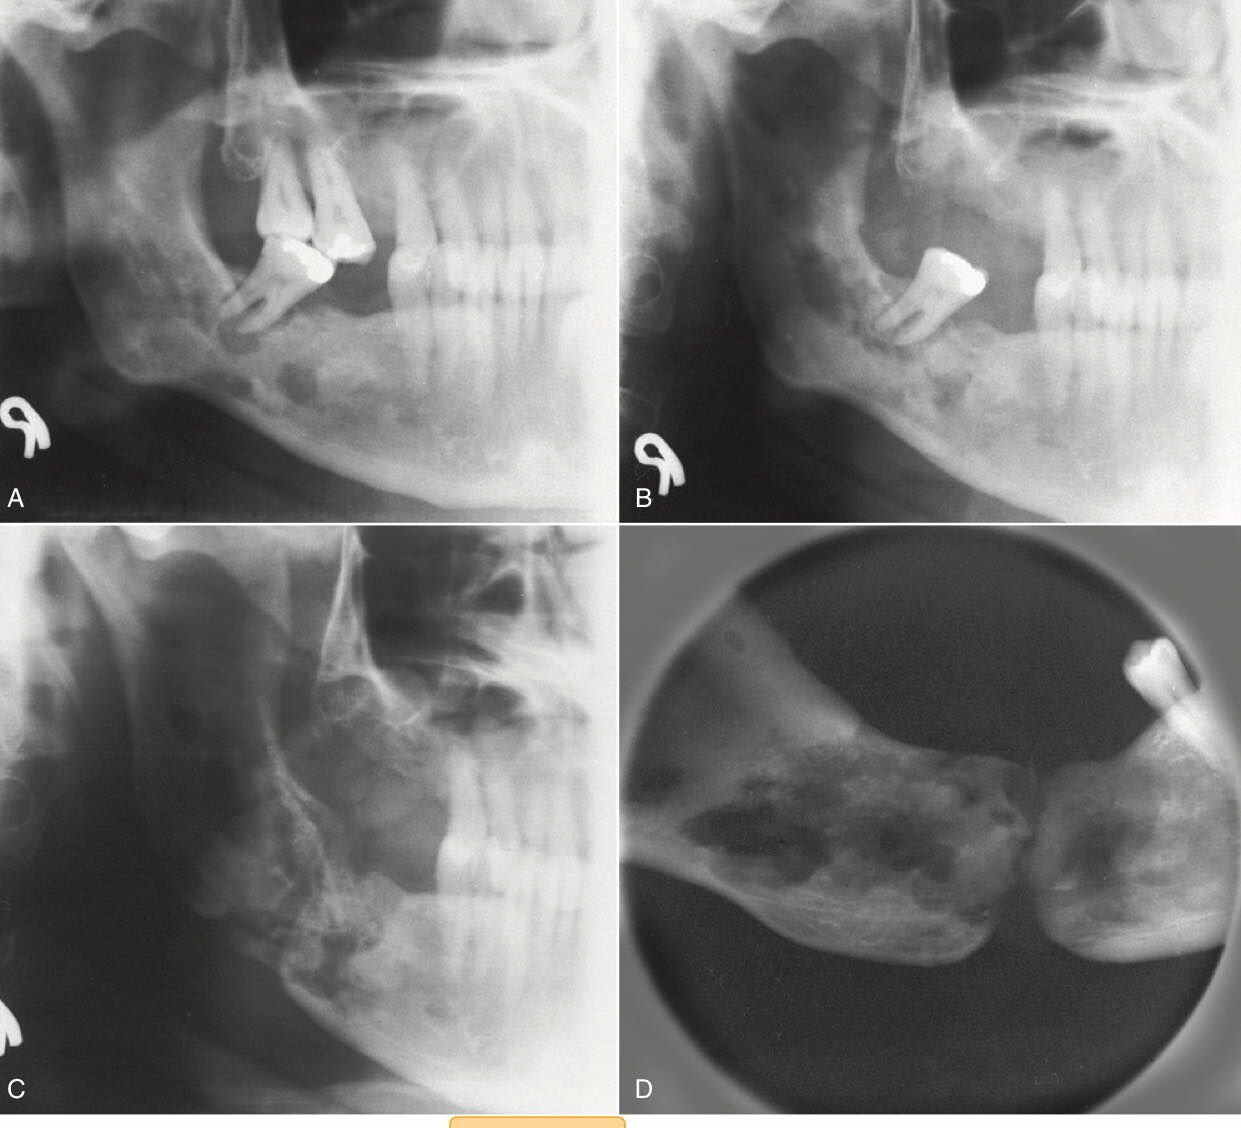

(B)在X光片檢查時,放射線骨壞死區域都呈現骨頭被蠶食(moth-eaten bone)的外觀

moth-eaten影像: SqCC,osteosarcoma,osteomylitis

orn影像:

課本沒有特別的形容詞,個人覺得比較適合的敘述是看得出原本的型態但聚集在一起的multiple RL